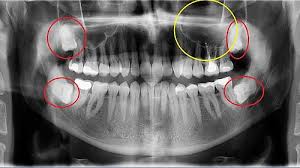

Der Arzt hat das unterste Stück der Wurzel stehen gelassen da es etwas verwachsen sei und zu nah am Nerv. Mir wurde am Mittwoch 214. Dieser entscheidet ob eine operative Entfernung des Zahnes notwendig ist.

Häufig verläuft ein Nerv entweder durch die Wurzeln oder am Zahn entlang. Und bei nicht wenigen war es der fall dass der eingriff nah am nerv vorgenommen wurde das risiko also da war. Bevor ich meinen körper über jahre mit schmerzmitteln schädige und schmerzen leide würde ich mich diesem eingriff unterziehen.

Sie liegen sehr nah am Nerv weshalb der Arzt nur zwei auf Einmal zieht. Bei der lokalen Narkose besteht das Risiko vor allem dadurch dass durch die Nadel ein Nerv beschädigt wird.

Das gilt auch für Nerven die um den Weisheitszahn liegen. Und bei nicht wenigen war es der fall dass der eingriff nah am nerv vorgenommen wurde das risiko also da war. Eine Entzündung des Weisheitszahns ist sehr schmerzhaft und äußert sich daneben häufig mit Rötung Schwellung und Eiterbildung. Bei mir sagte der arzt damals auch dass der nerv. Mir wurde am Mittwoch 214. Mir wurde vor 2 Jahren ein Weisheitszahn herausoperiert und dabei der Nerv verletzt. Nur jetzt heisst es das muss ein Spezialist machen weil der Zahn zu nah am Nerv ist. Hallo Zusammen seit ich ende august beim zahnarzt nach 5 jahren war wurde ein röntgen bild gemacht und dabei festgestellt das am retinierten weisheitszahn 48 ein zyste wahrscheinlich folikoläre ist. Ihr Zahnarzt setzt alles daran um diesen Nerv nicht zu.

Der Arzt hat das unterste Stück der Wurzel stehen gelassen da es etwas verwachsen sei und zu nah am Nerv. Meinem Sohn müssen alle vier Weisheitszähne gezogen werden damit hatte er sich ja abgefunden. Wie überstehe ich das nur. Weisheitszahn nah am Nerv. In meinem verwandten- und freundeskreis habe wirklich alle ihre weißheitszähne entfernen lassen und keinem ist was passiert. Weisheitszahn und zyste nerv nah - risiko. Ich hab gerade diese Frage gestellt.